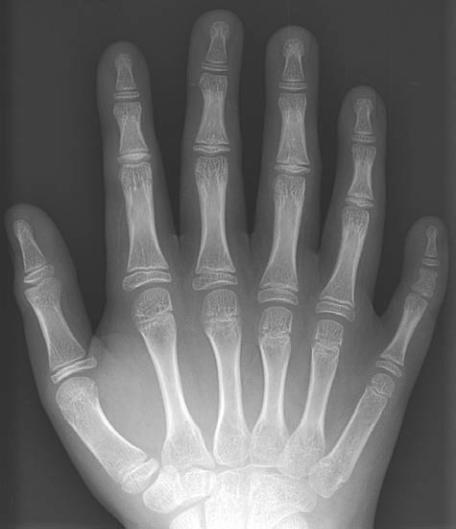

”. Tra gli Amish è molto frequente una

malattia genetica recessiva, la sindrome di Creveld,

che si manifesta con nanismo e polidattilia (più di

cinque dita per mano,

8

) ed è molto rara nel resto

Figura 8

Un gruppo di

donne Amish, comunità

che vive ancora secondo

rigide usanze (

a

);

radiografia della mano

di un bambino affetto da

polidattilia (

b

).